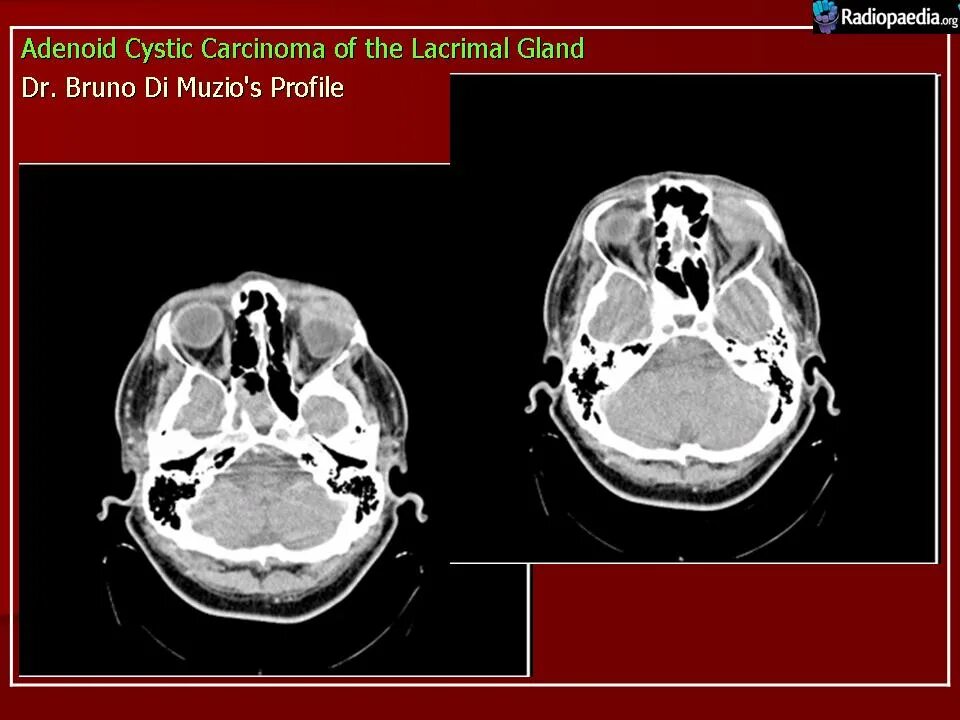

Кт пример